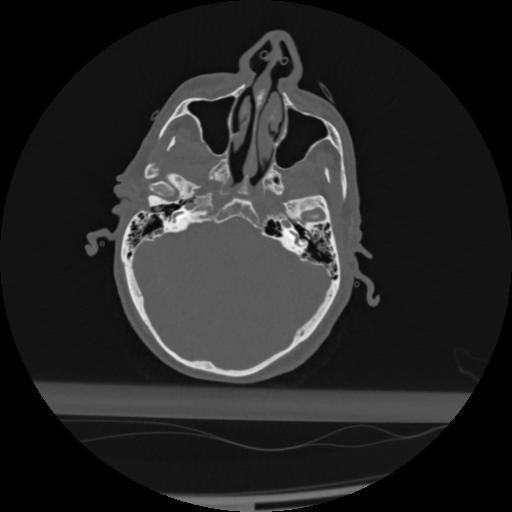

22 ANGIO,CE,Vol,0.5,ANGIO,,